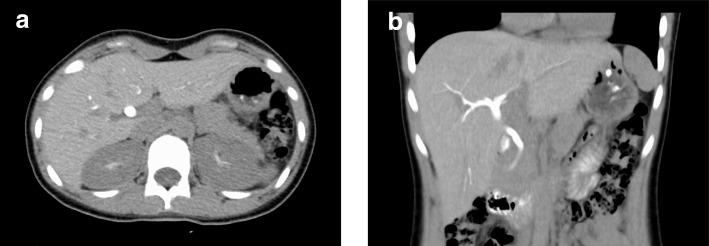

We describe a 13-year-old Japanese girl with a history of recurrent hepatic impairment, which had not been thoroughly investigated. She was referred to our hospital following 2 days of fever, fatigue, and abnormal blood tests suggested impaired liver function. Data from chest X-ray findings combined with a positive loop-mediated isothermal amplification assay result indicated Mycoplasma pneumoniae pneumonia, which was treated with oral azithromycin. To investigate potential hepatic impairment, we performed several imaging studies, namely, abdominal ultrasonography, magnetic resonance cholangiopancreatography, and contrast enhanced computed tomography. These imaging studies revealed a normal liver; however, the gallbladder was not in the usual nor any aberrant position in imaging investigations of the patient. Based on these results, we diagnosed gallbladder agenesis; however, the etiology of her hepatic impairment has not been elucidated.

我们描述了一例 13 岁日本女孩,她曾反复发作肝损伤,但未进行彻底检查。她因发热、疲劳和异常血液检查(提示肝功能受损)就诊于我院。胸部 X 线检查结果结合阳性环介导等温扩增检测结果提示肺炎支原体肺炎,给予口服阿奇霉素治疗。为了调查潜在的肝损伤,我们进行了几项影像学检查,包括腹部超声、磁共振胰胆管成像和增强计算机断层扫描。这些影像学检查显示肝脏正常,但胆囊在患者的影像学检查中并未出现在通常或任何异常位置。基于这些结果,我们诊断为胆囊缺如症;然而,她肝损伤的病因尚未明确。